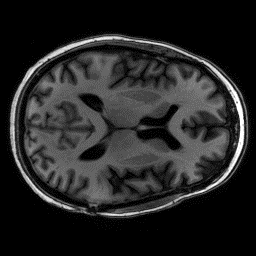

Reconstructing magnetic resonance (MR) images from undersampled data is a challenging problem due to various artifacts introduced by the under-sampling operation. Recent deep learning-based methods for MR image reconstruction usually leverage a generic auto-encoder architecture which captures low-level features at the initial layers and high?level features at the deeper layers. Such networks focus much on global features which may not be optimal to reconstruct the fully-sampled image. In this paper, we propose an Over-and-Under Complete Convolu?tional Recurrent Neural Network (OUCR), which consists of an overcomplete and an undercomplete Convolutional Recurrent Neural Network(CRNN). The overcomplete branch gives special attention in learning local structures by restraining the receptive field of the network. Combining it with the undercomplete branch leads to a network which focuses more on low-level features without losing out on the global structures. Extensive experiments on two datasets demonstrate that the proposed method achieves significant improvements over the compressed sensing and popular deep learning-based methods with less number of trainable parameters. Our code is available at https://github.com/guopengf/OUCR.